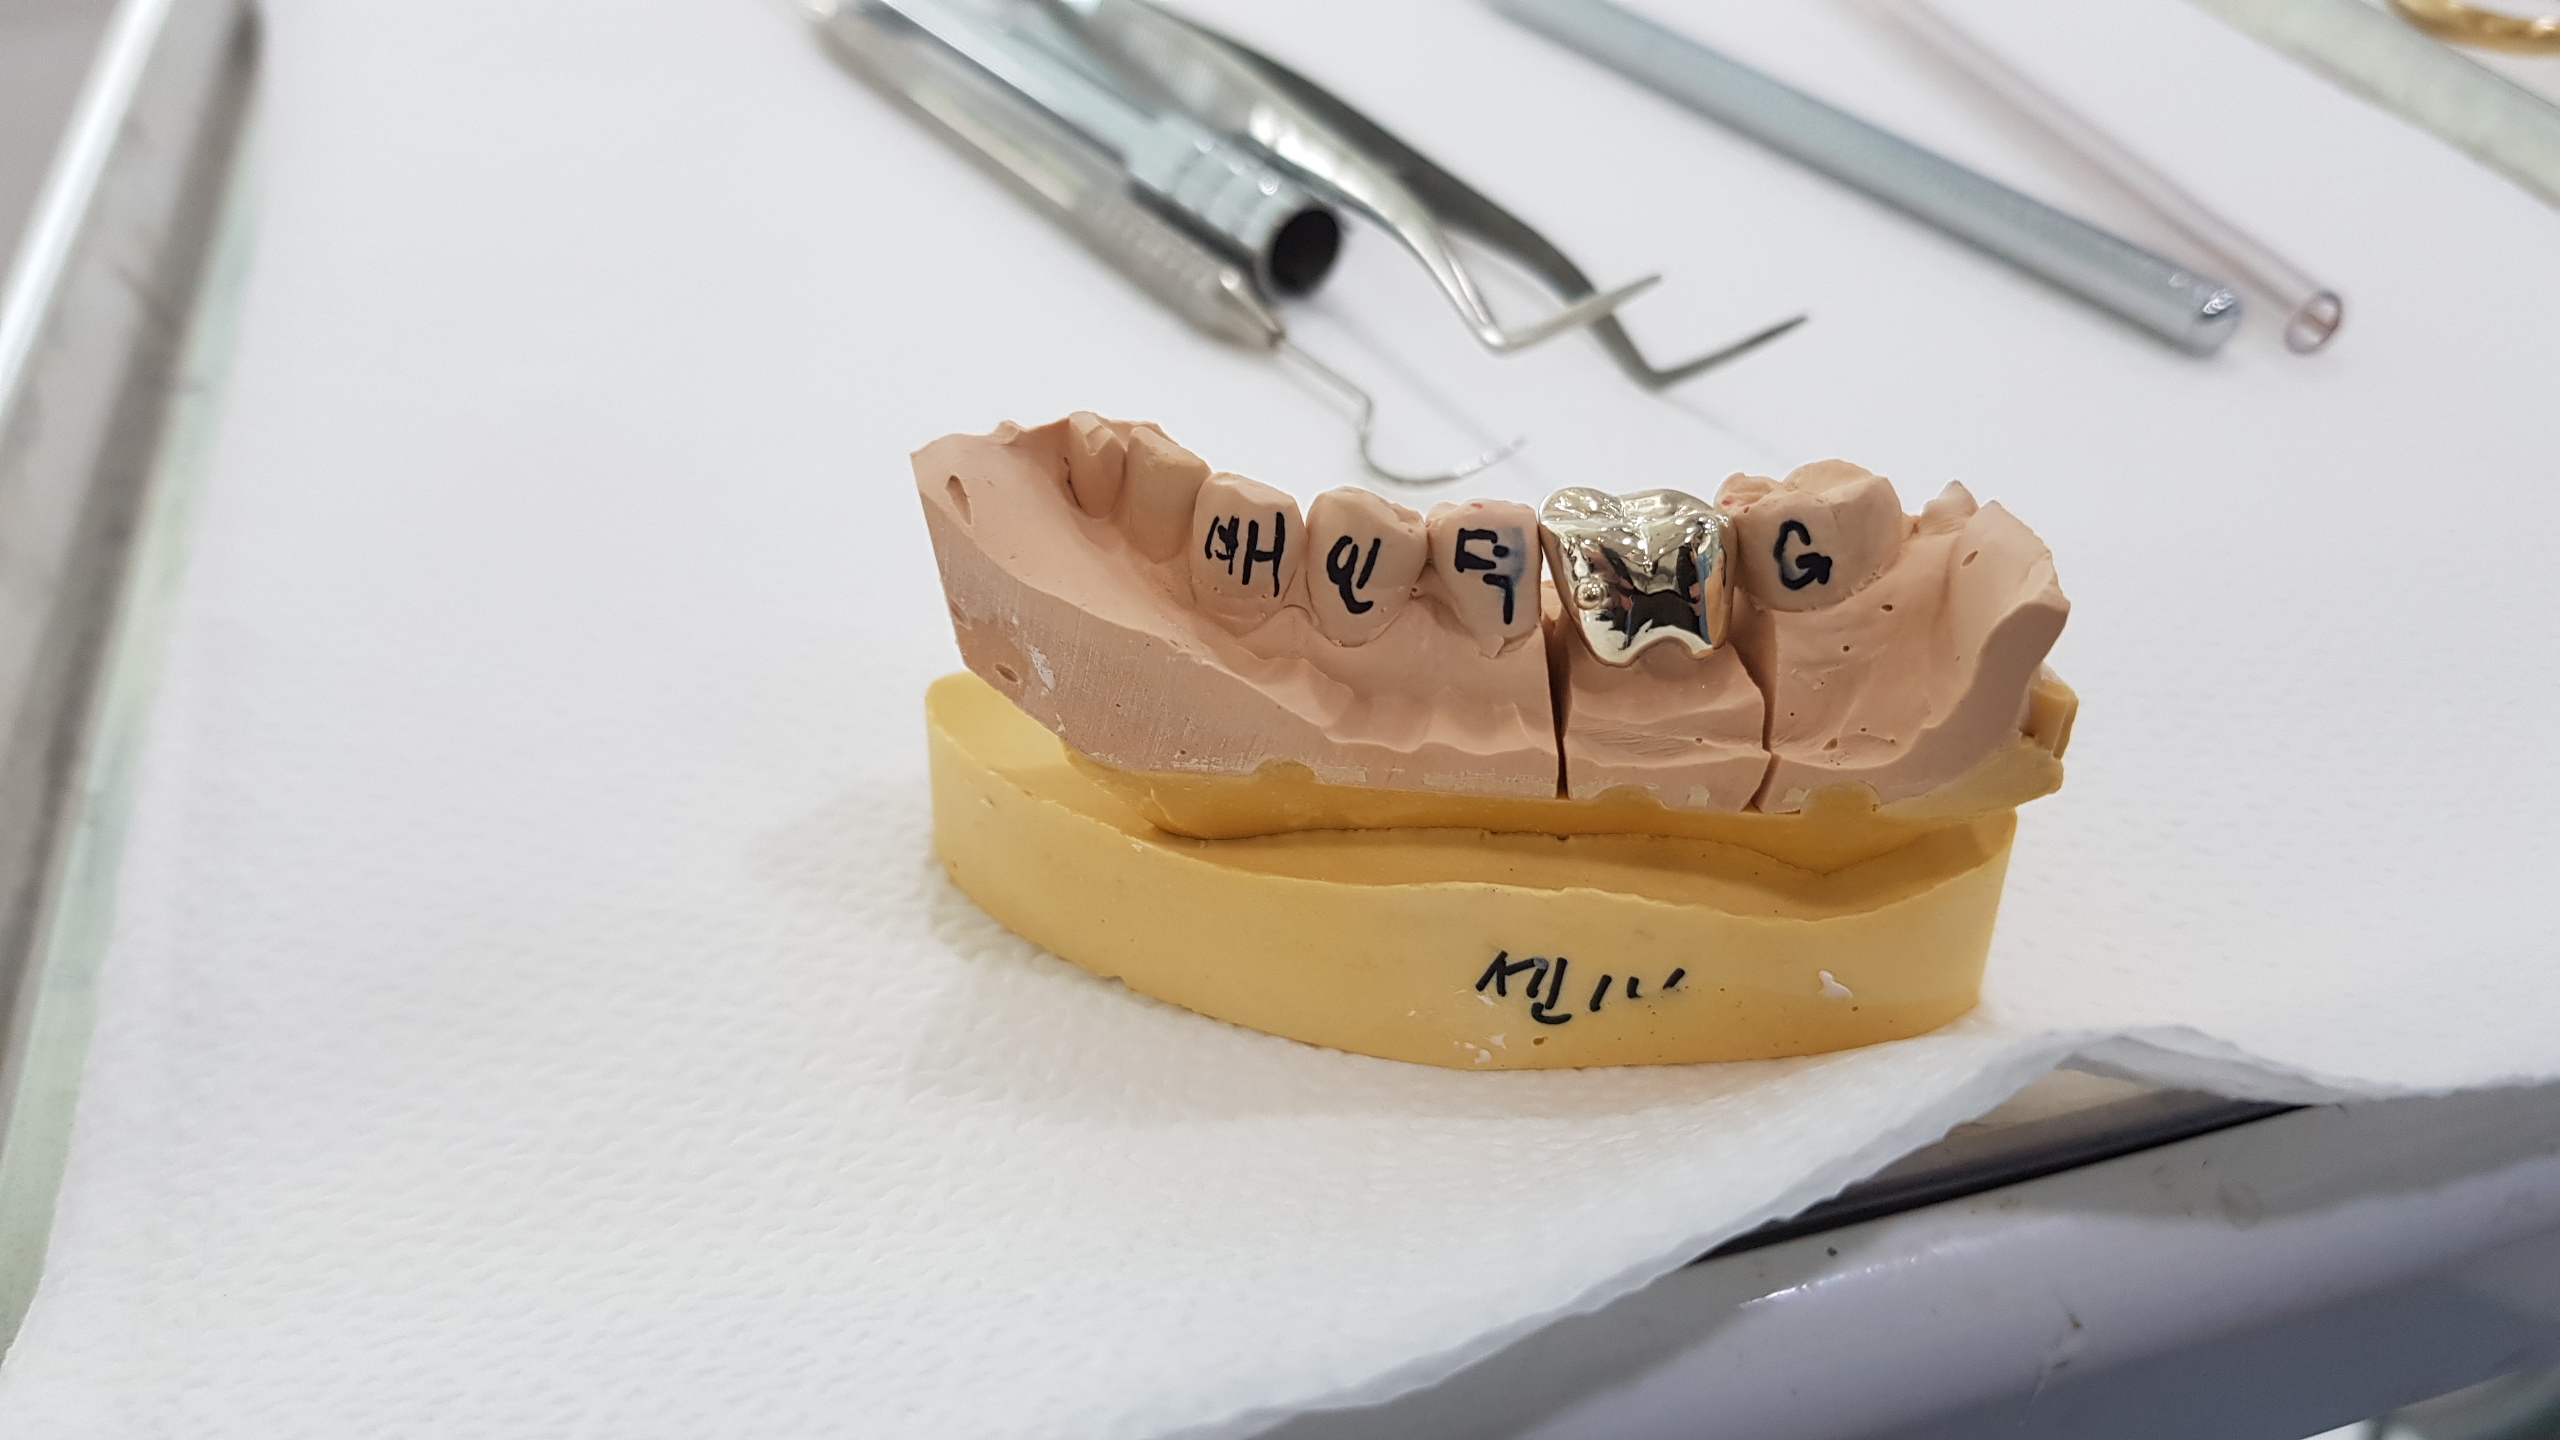

옆에 이빨의 본을 뜬 ..금이빨을 보여준다...

그래서 잽싸게 사진을 찍었다.